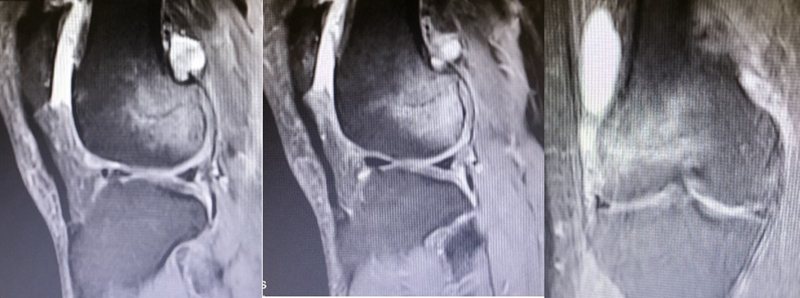

病例1:女,61岁,右膝关节诊断为Koshino Ⅲ期SONK,行右膝内侧单髁手术治疗。

(4)Koshino Ⅳ期SONK

由于存在继发退行性改变,一般不建议单纯行膝关节镜+自体骨软骨移植术。需在考虑5个因素的基础上兼顾患者年龄、性别和活跃程度,分别选择膝关节镜+HTO术+微骨折术、膝关节镜+HTO+坏死区病灶刮除+自体植骨术或单髁置换术。对于合并症状性髌股关节炎、外翻畸形、坏死区范围大影响单髁假体稳定性等的Koshino Ⅳ期膝关节股骨内侧髁SONK,采用全膝关节置换术。

病例1:男,64岁,主诉左膝关节内侧疼痛6年余。MR提示骨坏死区占比为33.28%,矢状位病变区域前后径为26.42mm,半月板相对突出百分比(RPE)31.78%,同时存在胫骨侧来源的下肢内翻畸形(MPTA83°),关节线会聚角2°。

行关节镜检查+软骨摘除+微骨折+HTO术,术后随访2年恢复良好,活动自如,行走时无左膝关节疼痛不适。

病例2:女,81岁,行内侧单髁手术治疗,术后恢复良好。